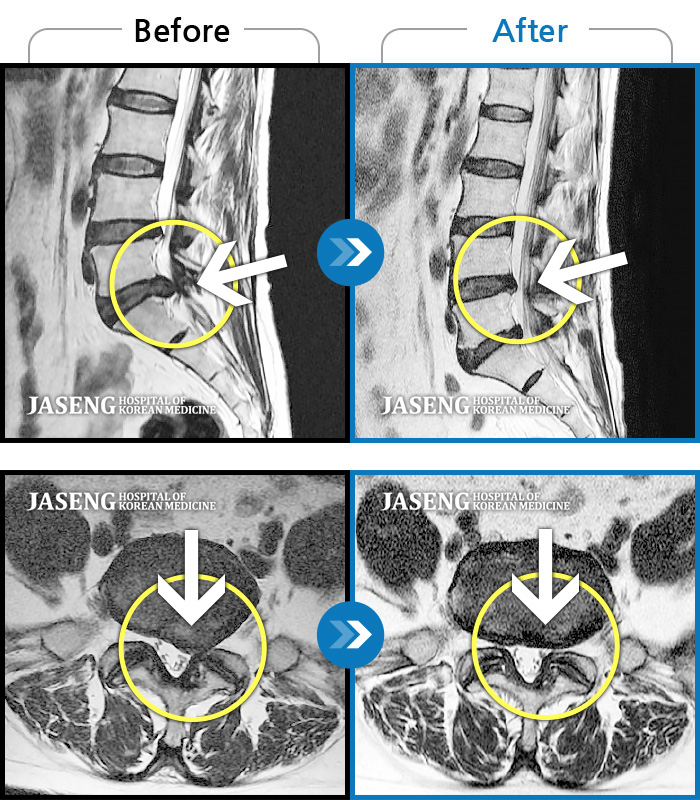

Before

After

허리통증, 골반 저림, 발가락 근력저하가 심하여 일상생활이 불가능한 상태

2023.05.19 ~ 2023.10.14